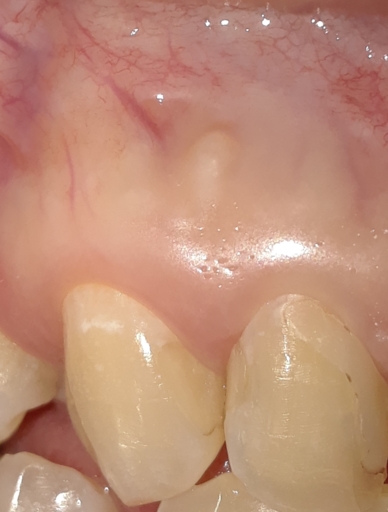

I had a root canal in May. I went to the dentist to fill my tooth and he filled my tooth too much according to my endodontist, she has it on an x Ray that the endodontist took. Now I am on antibiotics

It is possible that over filling a tooth during a root canal can cause inflammation of the periodontal ligament, which results in tenderness and pain.  A small amount of gutta percha or sealer wil be okay, however every person is different as is every tooth.  Healing will be different in each person.  It is best to take the antibiotics as directed and stick to a soft diet until the tooth is healed in order to keep pressure off the tooth.

Does over filling the tooth after a root canal cause inflammation and pain